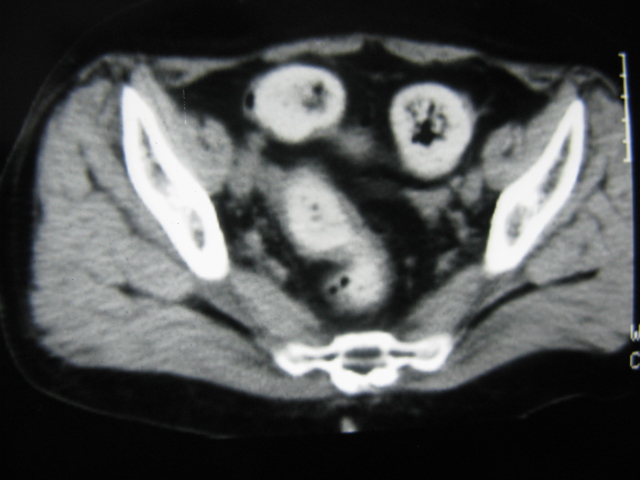

患者,女,64岁,2002年诊断为宫颈癌,当时只做过放,化疗。现在诊断:(1)宫颈癌。(2)直肠癌。请同道们讨论,探讨。另外肠壁为啥密度这么高,ct值约112hu。患者没有做过增强和造影。

高密度的不是肠管影,是肠管内的粪便影

患者直肠病变,排便不畅,粪便硬结造成,更高密度如钡灌肠者都可出现

硬结粪便能有如此高密度影?

我也碰到过几例,最离奇的一例是全结肠呈造影样高密度,患者直肠癌(首次发现),以往没有吃药,只有约半年时间长的胃纳差,排便不畅(据患者说每次大便只能拉出少许黄水)

不一定有意义,可清洁灌肠后复查